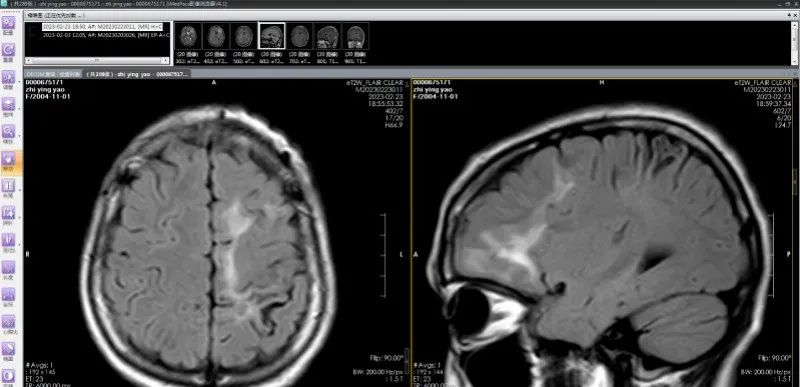

脑软化灶实为虫体在颅内的爬行轨迹;(左)从下往上移动,(右)从后往前移动

神外医生手术抓取11厘米长活虫

通过间隔2周的观察,团队最终精准定位到寄生虫位于患者左侧额叶前部,并在三维脑上描记了虫体位置。随后,团队为患者实施寄生虫抓取及肉芽肿切除术,顺利“活捉”一条长约11厘米的裂头蚴,连同“虫窝”也一并切除了。